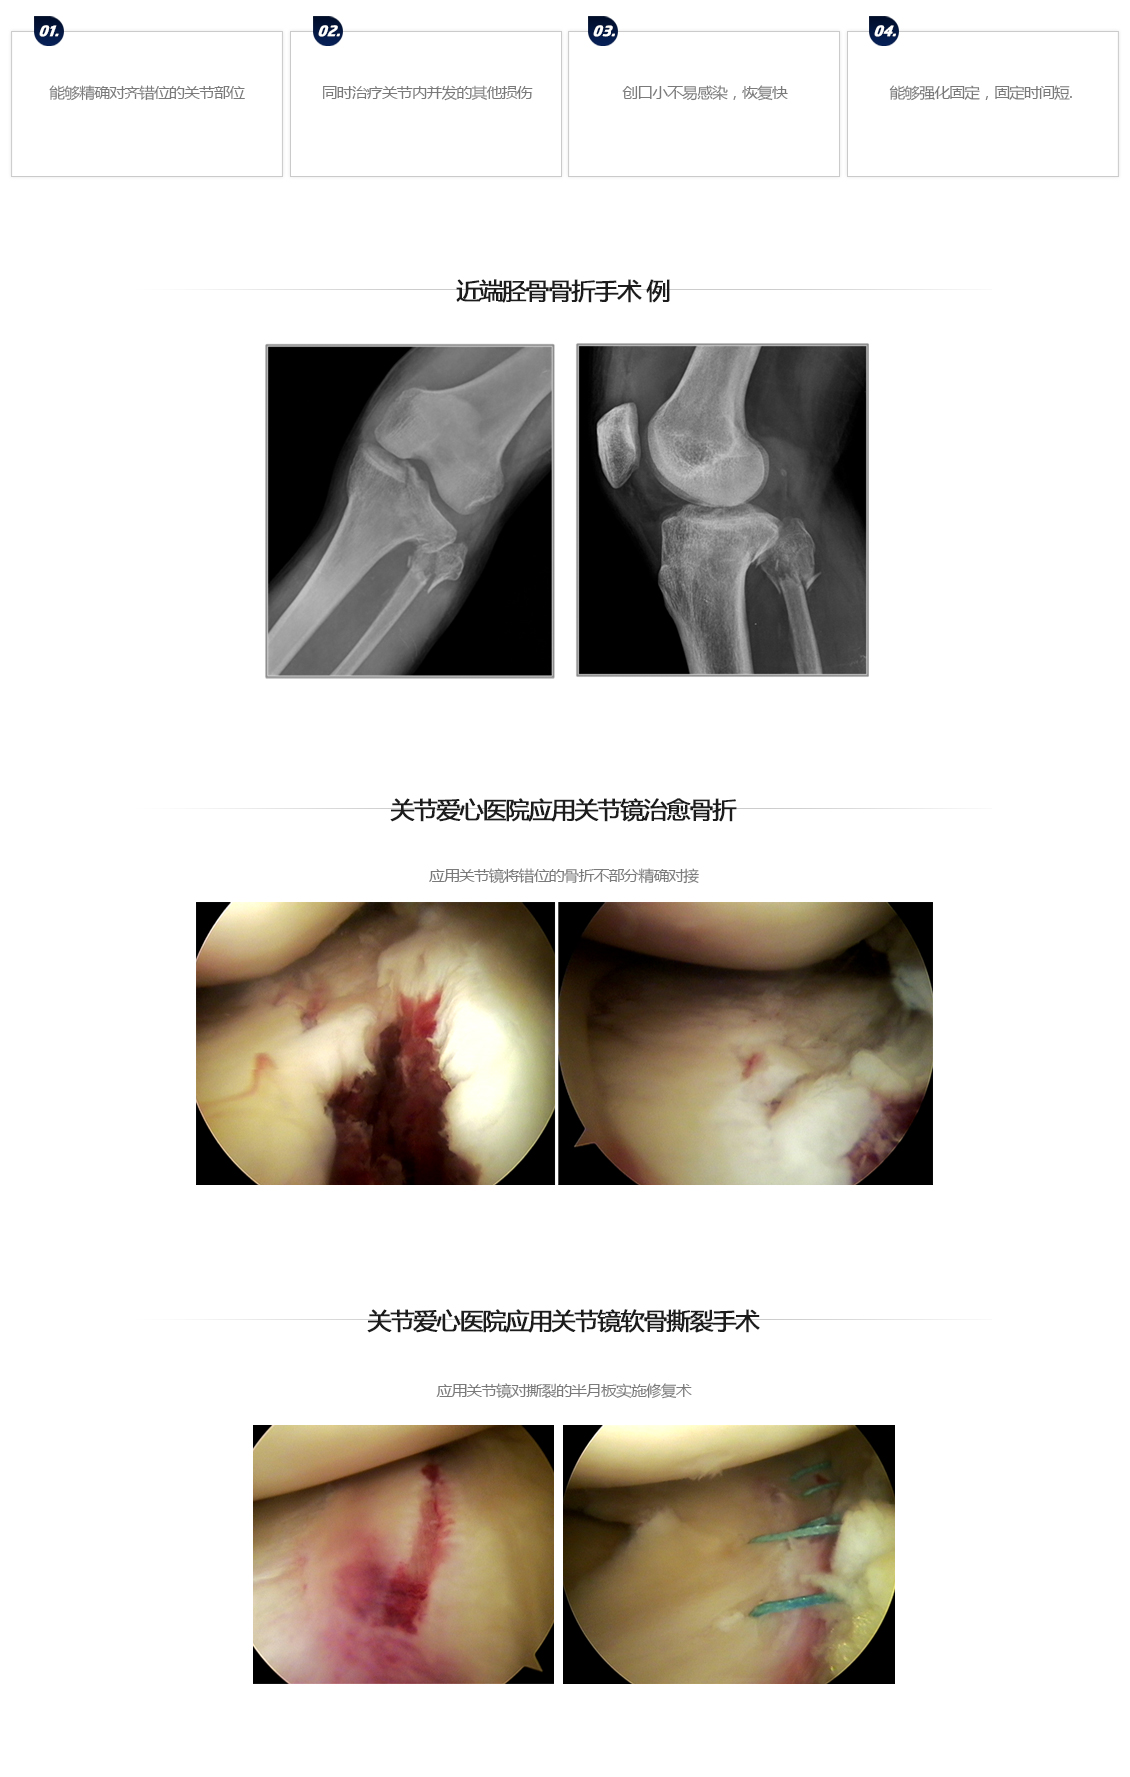

膝盖骨折手术